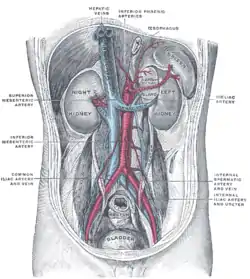

Renal arteries branching left and right from the aorta (in red) | |

The renal arteries are paired arteries that supply the kidneys with blood. Each is directed across the crus of the diaphragm, so as to form nearly a right angle.

The renal arteries normally arise at a 90° angle off of the left interior side of the abdominal aorta, immediately below the superior mesenteric artery.[1] They have a radius of approximately 0.25 cm,[2] 0.26 cm at the root.[3] The measured mean diameter can differ depending on the imaging method used. For example, the diameter was found to be 5.04 ± 0.74 mm using ultrasound but 5.68 ± 1.19 mm using angiography.[4][5]

Due to the anatomical position of the aorta, the inferior vena cava, and the kidneys, the right renal artery is normally longer than the left renal artery.[1][6]

- The right passes behind the inferior vena cava, the right renal vein, the head of the pancreas, and the descending part of the duodenum. It’s somewhat lower than the left one.

- Left artery lies behind the left renal vein, the body of the pancreas and the splenic vein, and is crossed by the inferior mesenteric vein.